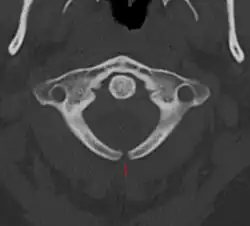

Meningocel

Meningocelul este forma cea mai rară a spinei bifide, se mai numește și chist meningeal. Meningocelul afectează meningele(membrana care acoperă măduva spinării) și care iese(herniază) printr-o breșă, formând un mic sac, care se numește meningocel (în limba greacă meminx=membrană, kele=umflătură).

În cazul meningocelului posterior vertebra se dezvoltă normal, cu toate acestea, meningele herniază între vertebre. Dacă sistemul nervos rămâne neafectat, sunt șanse mici ca bolnavul să prezinte probleme de sănătate pe termen lung.